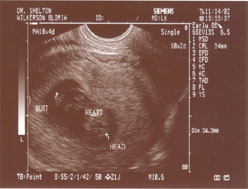

PICTURE 1:

The afternoon couldn't come fast enough

for me. We had an appointment at Dr.

Koristoff's office to have my very first

ultrasound done. This picture here was the

first they took. The detail of what

we could see was amazing, even at 10

weeks. The heart was aflutter, and

what will be our baby's arms were swinging

around, almost waving. What a neat,

special experience. |